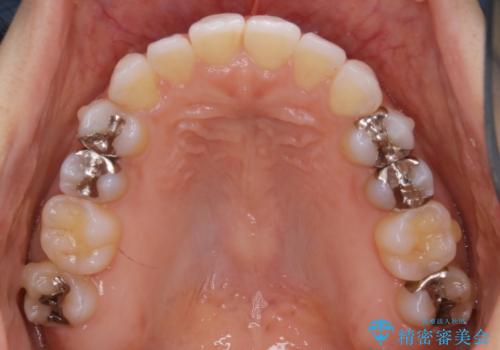

- 前歯のガタつき改善を主訴にご来院されました。

ガタつき自体は軽度で、奥歯の噛み合わせのズレもほとんどなかったため、非抜歯でマウスピース矯正装置を選択しました。

歯列の幅の拡大と歯を小さくする調整を行うことで並べるスペースの確保を行いました。この方法は、ガタつきをとりたいところに直接スペースを作ることができるので治療期間を短縮することができ効率的です。

歯列弓の拡大

歯並びが悪くなる原因の一つに「歯列弓の狭窄」というものがあります。

奥歯や前歯が内側(舌側)に倒れ込んでしまったり、歯が生えてくる位置が内側になってしまうことにより歯並びのアーチが狭くなってしまうことを言います。

このような場合、歯並びのアーチを拡大してあげるだけでもガタつきを無くすためのスペースがかなり作れることがあります。